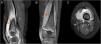

MR of the left knee was performed (Fig. 1) which revealed synovitis and an extensive hyperintense imaging in the STIR sequences with homogeneic enhancement after the administration of intravenous contrast (IVC) in internal and external vessel, compatible with pyomyositis.

MR imaging of the left knee, STIR sequences with intravenous contrast (IVC). (A) Sagittal slice. (B) Coronal slice. (C) Transversal slice. Major synovitis is observed which affects the suprapatellar bursa (arrows) and muscular hyperintensity of the internal and external vastus lateralis muscles. Compatible with pyomyositis (star).